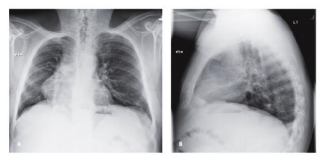

Paciente masculino de 25 anos de idade com achado

incidental em radiografia de tórax (CXR). Diante de tal caso,

o diagnóstico mais provável é: